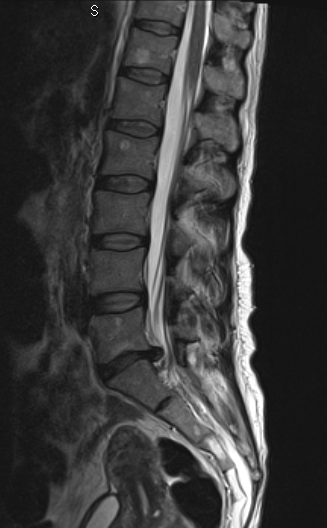

La paciente fue intervenida con un abordaje posterior medial (incisión de 3-4 cm) y con técnica microquirúrgica se realizó una discectomía L5-S1 derecha, preparación de disco y colocación de prótesis intersomática de titanio asociada a fijación transfacetaria. Obsérvese en la imagen anterior la adecuada alineación de facetas así como una adecuada amplitud de las mismas para realizar una fijación transfacetaria bilateral. En el caso que hubiésemos tenido que quitar mucha faceta ipsilateral o esta se hubiese fracturado, habríamos completado la fusión con dos tornillos transpediculares.